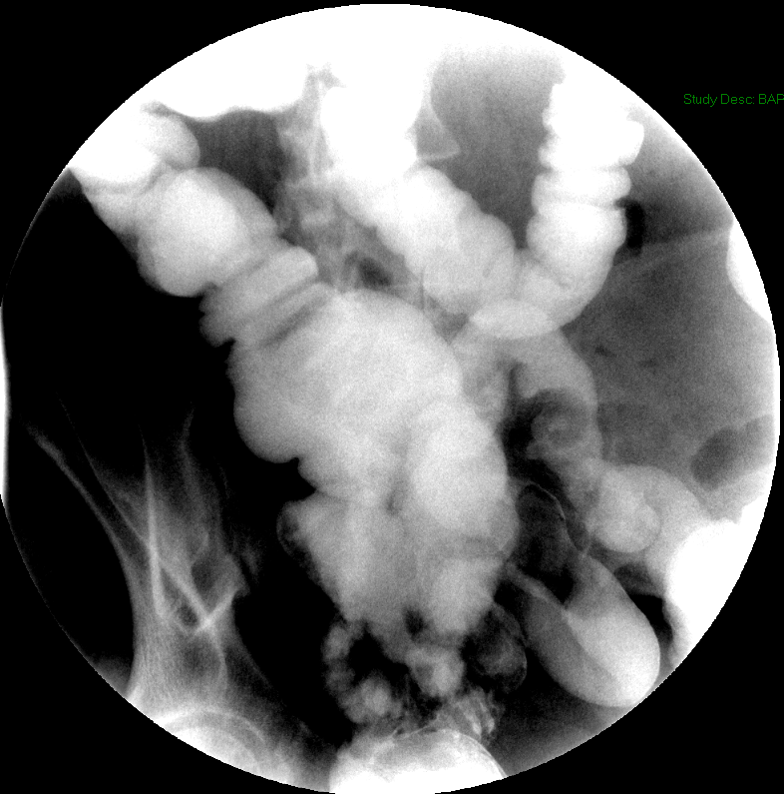

- Once the barium has reached the small bowel, you will go into the room and obtain spot images of the contrast material filled small bowel.

- Obtain images of the terminal ileum and the ileocecal valve filled with contrast material

(key image 6)

(key image 7)

(key image 8)

(key image 9)

(key image 10).

- Obtain spot images of the remainder of the small bowel

(key image 11)

(key image 12)

(key image 13)

(key image 14).

- Obtain images of all four quadrants. Use the compression paddle to separate loops of small bowel from each other.

- Evaluate for tethering of small bowel to any other structures.

- Observe for small bowel peristalsis.